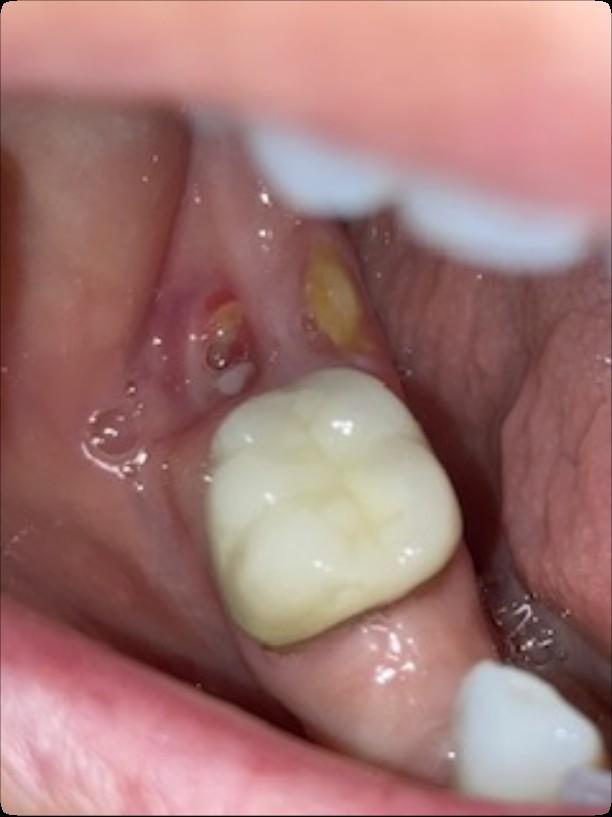

Osteonecrosis of the Jaw

MRONJ: Medication Related Osteonecrosis of the Jaw

• Rare oral side effect called osteonecrosis of the jaw that is associated with certain medications, bone-modifying agents.

• Osteonecrosis of the jaw is a condition where small area(s) of the jawbone have difficulty healing and the bone starts to breakdown and die.

How Common is MRONJ?

The risk is thought to be less than 1% for patients taking IV bonemodifying agents, and at least ten times less likely than that for patients taking the drugs by mouth.

If I take these medications, am I automatically at risk?

• Anyone who takes these medications has a chance of developing ONJ.

• However, most reported cases occur after a type of oral “injury” – which could a tooth extraction, chronic periodontal (gum) disease, an oral surgical procedure, or simply a nonhealing traumatic ulceration.

• Tobacco use, treatment with corticosteroids, long-term use of bonemodifying agents, and diabetes also may increase the risk of this condition occurring.

What are the signs of MRONJ?

• The hallmarks of ONJ are exposed bone or gum/mucosa/tissue wounds that heal very slowly or do not heal at all for eight weeks or more after an injury to the mouth.

• Some patients report that this begins with a feeling of “roughness” on the gum tissue. If these open wounds become infected, there may be pus or swelling in the adjacent gum tissue.

• Many times, this condition is painless in the beginning, and patients only experience pain after the exposed bone becomes infected.

How is MRONJ treated?

• Education

• Careful oral hygiene

• Conservative interventions

• Avoid surgical intervention, if possible

• PATIENCE!